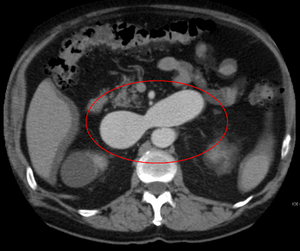

يتم تشخيص التشوه الشرياني الوريدي بشكل أساسي من خلال طرق التصوير التالية:

- التصوير المقطعي المحوسب (CT) هو عبارة عن أشعة سينية غير باضعة لعرض الهياكل التشريحية داخل الدماغ لاكتشاف الدم في الدماغ أو حوله. تتضمن تقنية أحدث تسمى تصوير الأوعية المقطعية المحوسبة حقن التباين في مجرى الدم لعرض شرايين الدماغ. يوفر هذا النوع من الاختبارات أفضل صور الأوعية الدموية من خلال تصوير الأوعية والأنسجة الرخوة من خلال التصوير المقطعي المحوسب.

- يعد التصوير بالرنين المغناطيسي (MRI) اختبارًا غير باضع ، يستخدم مجالًا مغناطيسيًا وموجات تردد الراديو لإعطاء رؤية مفصلة للأنسجة الرخوة للدماغ.

- تصوير الأوعية بالرنين المغناطيسي (MRA) - فحوصات تم إنشاؤها باستخدام التصوير بالرنين المغناطيسي لتصوير الأوعية الدموية وهياكل الدماغ على وجه التحديد. يمكن أن يكون تصوير الأوعية بالرنين المغناطيسي إجراءً جائرًا ، يتضمن إدخال صبغات التباين (على سبيل المثال ، عوامل تباين الجادولينيوم MR) في الأوعية الدموية للمريض باستخدام قسطرة يتم إدخالها في الشريان وتمريرها عبر الأوعية الدموية إلى الدماغ. بمجرد وضع القسطرة في مكانها ، يتم حقن صبغة التباين في مجرى الدم ويتم التقاط صور التصوير بالرنين المغناطيسي. بالإضافة إلى ذلك أو بدلاً من ذلك ، يمكن استخدام تقنيات التصوير بالرنين المغناطيسي المعتمدة على التدفق أو غيرها من تقنيات التصوير بالرنين المغناطيسي لتحديد الموقع والخصائص الأخرى للأوعية الدموية

يمكن أن تحدث التَشوّهات الشريانية الوريدية في أجزاء مختلفة من الجسم:

- كبد[15]